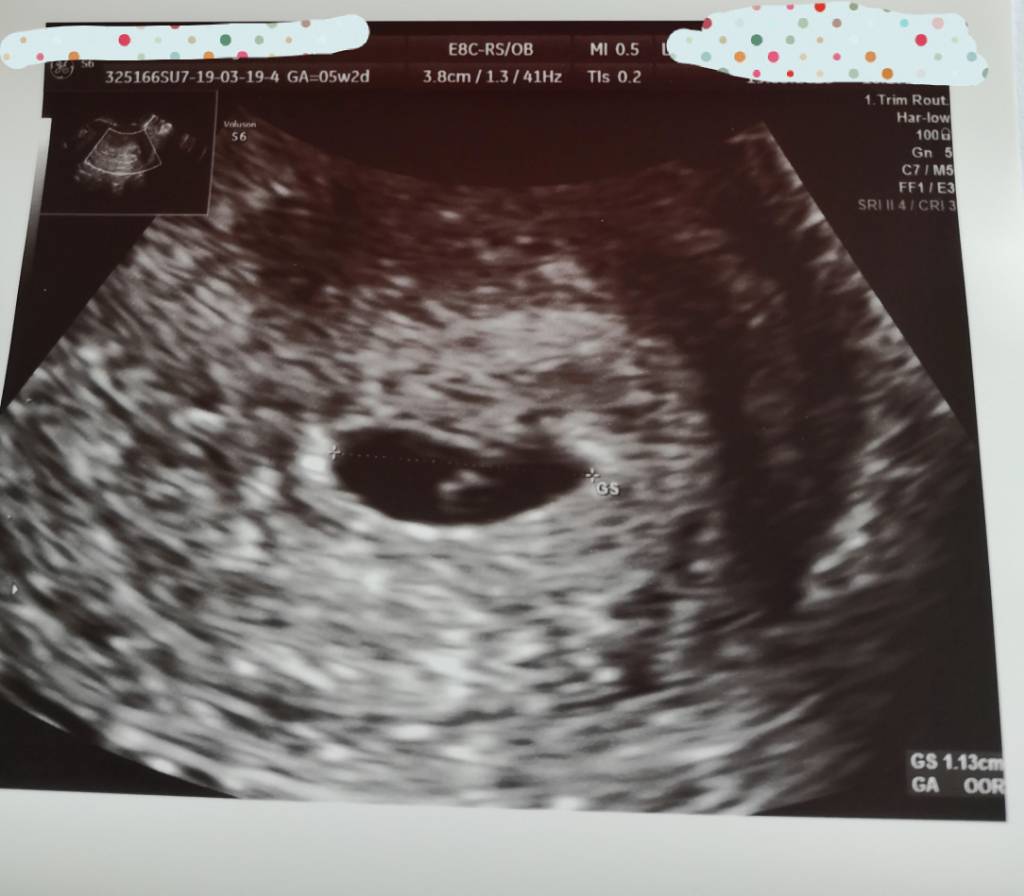

Powiedzcie mi te 7.0cm/2.6 to co to za wymiary? Pecherzyk i zarodek? Bo nie dopytalam lekarza z tego wszystkiego

No właśnie nie mam hmm [emoji848] ale to taki sprzęt na NFZ, jakiś kosmiczny nie byłGratulacje, supera masz jakieś oznaczenia na tym USG? Długość zarodka to CRL, GS to chyba pęcherzyk ciążowy, a YS ciałko żółte.

U mnie widać oznaczenia długość tak: